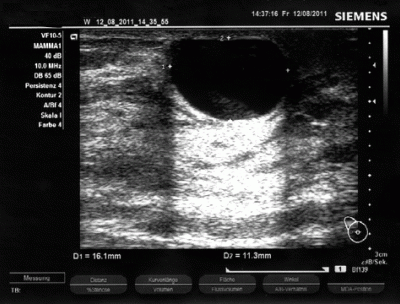

Gesundes Brustdrüsengewebe